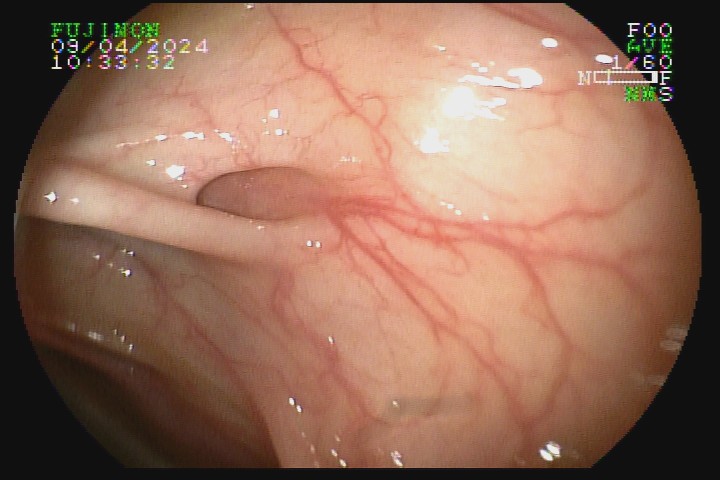

A diverticulose cólica é consequência da herniação da mucosa do intestino grosso por entre as fibras musculares da parede intestinal. A diverticulose do cólon esquerdo complica mais com inflamação, e a diverticulose do cólon direito complica mais com sangramento.

Atlas de Endoscopia Digestiva da SOBED/Marcelo Averbach, Huang Ling Lang, Luis Masúo Maruta et al. - 2. Ed. - Rio de Janeiro - RJ: Thieme Revinter Publicações, 2020.